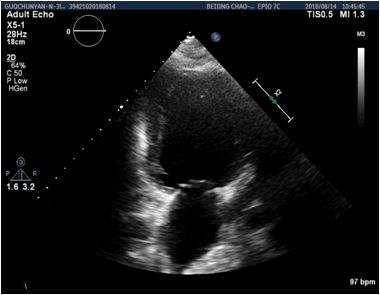

重症超声

1、下腔静脉变异度11 %

2、右心无增大

3、左室收缩功能降低(EF=47% FS=28% EDV=112ml SV=52ml)

4、肺部超声肺间质综合征